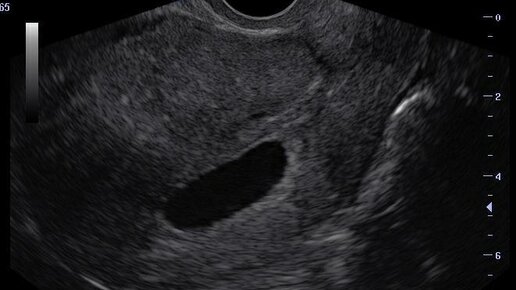

Стоит ли делать УЗИ на ранних сроках беременности

С чего все началось  Когда я узнала, что беременна сразу пошла записываться на прием к врачу. Так как моя запись подойдёт только через две недели, я решила сделать УЗИ, чтобы уже с достоверными фактами идти на прием к врачу. Немного предыстории  В прошлом году у меня на ранних сроках была замершая беременность. Я, все как положено, встала на учёт в женской консультации и меня отправили записываться на первое УЗИ и скрининг. Но при записи у нас с врачом получилось разногласие в сроках беременности и чтобы доказать свою правоту я пошла на платное УЗИ...

Сколько раз делать УЗИ за беременность?

Ультразвуковое исследование или УЗИ – это на сегодняшний день один из самых распространённых способов обследования беременной женщины, которое позволяет определить правильность и своевременность физиологического развития плода, а также пуповины, плаценты, околоплодных вод, матки и шейки матки. Именно на УЗИ можно увидеть предпосылки для того или иного вида родоразрешения. УЗИ во время беременности – что это и как проводится? УЗИ во время беременности – или сонография – неинвазивный (не нарушающий целостность организма) метод исследования развивающегося в утробе матери плода...